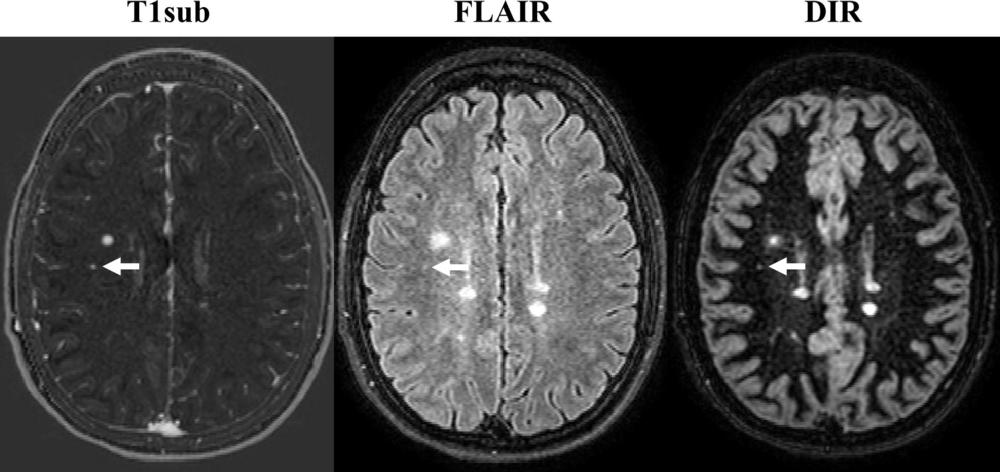

Dr. Wiestler credited an image subtraction pipeline developed and researched at his facility for the powerful sensitivity of the non-contrast MRI in detecting newly occurring lesions. The approach combines 3-D MRI and subtraction techniques, which cancel out unchanged areas in the follow-up image, substantially improving visualization of new or enlarging white matter lesions.

This combination of 3-D sequences and subtraction techniques is key to improving sensitivity for detecting newly occurred lesions, Dr. Wiestler said.